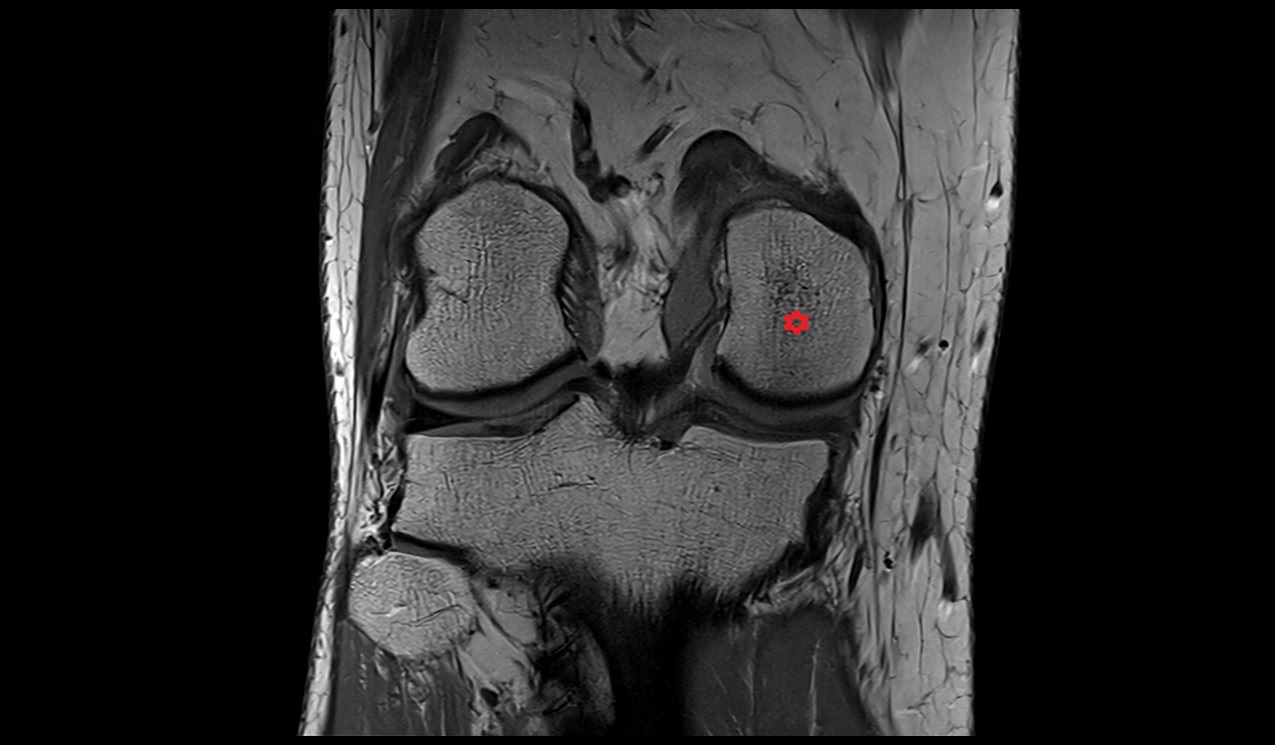

- Lateral condyle of femur

- Medial condyle of femur

- Medial epicondyle of femur

- Lateral epicondyle of femur

- Femoral condyle articular cartilage

- Tibial condyle articular cartilage

- Knee Joint

- Medial collateral ligament

- Lateral collateral ligament